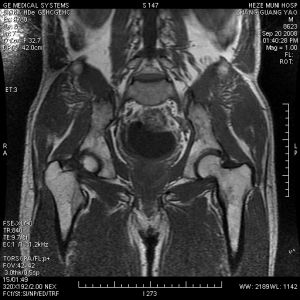

④淋菌性盆腔炎性疾病(gonococcalpelvicinflammatorydisease,GPID):包括急性輸卵管炎、子宮內膜炎、繼發性輸卵管卵巢膿腫、盆腔腹膜炎和盆腔膿腫等。10%~15%的淋菌性子宮內膜炎可上行感染,發生淋菌性盆腔炎、輸卵管炎、卵巢炎、附屬檔案炎及宮體炎。可引起輸卵管阻塞、積水及不孕。如與卵巢粘連,可導致輸卵管卵巢膿腫,一旦膿腫破裂可引起化膿性腹膜炎。66%~77%的盆腔炎多發生於月經後,主要見於年輕育齡婦女。典型症狀為雙側下腹劇痛,一側較重,發熱、全身不適,發熱前可有寒戰,常伴食欲不振、噁心和嘔吐。患者多有月經延長或不規則陰道出血,膿性白帶增多等。